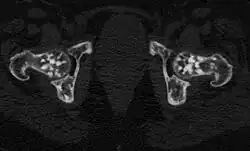

Die Osteopoikilose (auch: Osteopathia condensans disseminata, Osteopoikilie) ist eine seltene, gutartige, meist zufällig entdeckte Knochenfehlbildung. Dabei finden sich im Becken und in den Meta- und Epiphysen sowie in den Hand- und Fußwurzelknochen Cluster-artig viele, unregelmäßige, runde bis ovale Verdichtungszonen der Spongiosa von wenigen Millimetern bis Zentimetern. Die Veränderungen finden sich seltener in der Diaphyse. Oft ist das Verteilungsmuster symmetrisch. Schädel und Wirbelsäule sind selten betroffen. Die Herde gehen ohne klare Grenze in die Umgebung über. Die Kompakta ist nicht betroffen.

In einer der größten Untersuchungen zur Osteopoikilose, einer türkischen Studie von 1992,[3] fanden sich ausgehend von vier Patienten, bei denen die Osteopoikilose zufällig gefunden wurde, bei Untersuchung der Familienangehörigen schließlich 49 weitere Fälle (insgesamt 33 Männer und 20 Frauen, Verhältnis 1,65:1). Anhand der Stammbäume wurde in diesen Familien aus Ost-Anatolien und der Schwarzmeergegend eine autosomal-dominante Vererbung aufgezeigt. Bei 51 von 53 Patienten war die Osteopoikilose beidseitig. Betroffen waren vorwiegend die Metaphysen, sowie die benachbarten Knochenregionen, ohne Unterschied zwischen distalen und proximalen Metaphysen. Die Skleroseherde fanden sich in absteigender Häufigkeit in den Fingerknochen (Phalangen, 100 %), Handwurzelknochen (Carpalia, 97,4 %), Mittelhandknochen (Metacarpalia, 92,3 %), Zehenknochen (Phalangen, 87,2 %), Mittelfußknochen (Metatarsalia, 84,4 %), Fußwurzelknochen (Tarsalia, 84,6 %), gefolgt von Becken (74,4 %), Oberschenkelknochen (Femur, 74,4 %), Speiche (Radius, 66,7 %), Elle (Ulna, 66,7 %), Kreuzbein (Sacrum, 58,9 %), Oberarmknochen (Humerus, 28,2 %), Schienbein (Tibia 20,5 %) und Wadenbein (Fibula, 12,8 %).